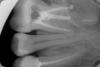

p3vlad Опубликовано 5 июня, 2012 Поделиться Опубликовано 5 июня, 2012 господа,нужен ваш совет-прогноз относительно моей 6-ки.6-ка была запломбирована,дырок не было.Внезапно зуб начал болеть, пошла к врачу. Мне поставили диагноз обострение хронического периодонтита. Сказали,что у меня огромная киста в корнях 6-ки и гранулёма в районе 5-ки.Начали лечение.зуб вскрыли,прошли каналы. Из 4 - х каналов сделали 3,врач утверждает,что 4-й канал зарос и трогать его не нужно.Положили лекарство,отправили гулять на 2 недели с веременной пломбой.Второй прием-снова дооолго прочищали-промывали каналы, положили лекарство, сделали временную пломбировку 3-х каналов,отправили гулять на месяц с временной пломбой. В конце июня планируется постоянная пломбировка каналов и постановка коронки,т.к. такую большую пломбу врач ставить не берется,точнее без гарантии за лечение.Вопрос следующий - правильно ли поставлен диагноз?Нужно ли пытаться расширить 4-й канал или реально можно так его оставить?не появится ли снова проблемы из-за этого нераскрытого и непройденного канала?плюс еще доп вопрос - сразу же после начала лечения, в районе соседней пятерке на внешней стороне десны появилось белёсое уплотнение,как шишка..Что это может быть?пока никаких неприятностей от неё нет - не болит, ничего оттуда не течет.Что это может быть?прикладываю снимки..нужен ваш прогноз - имеет ли смысл это всё лечить (уже выкинуто 10 тыс рэ,но есть сомнения,что выкинуты они именно что на ветер)?Или лучше сразу удалить 6-ку и крутить имплант.С другой 6-й на верхней челюсти была лет 6 назад такая же беда - киста,периодонтит.Пролечили,зуб восстановили,через 2 недели сильное обострение,зуб удалили и цинично пригласили на имплантацию....Есть ли какие-то гарантии,что история 6-летней давности не повторится вновь? Ссылка на комментарий

dok1 Опубликовано 5 июня, 2012 Поделиться Опубликовано 5 июня, 2012 Раскрывать нужно всегда и все каналы, деньги выкинуты не на ветер, и что-то не видать ОГРОМНЫХ кист и гранулём. Маленькие разряжения есть, 4 канал что-то не очень прослеживается.В общем прогноз у зуба хороший. Ссылка на комментарий